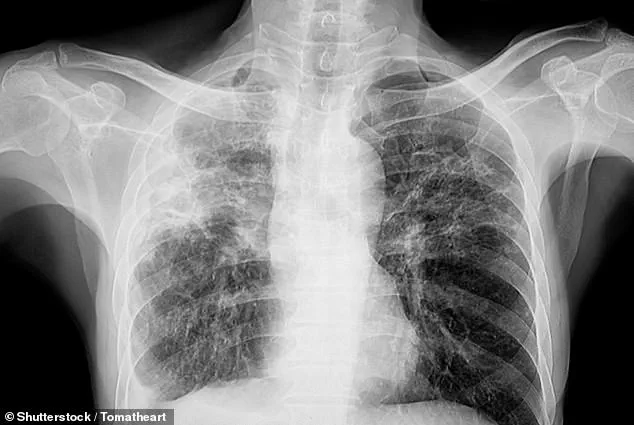

More than 70,000 Britons are currently living with pulmonary fibrosis, a chronic disease which causes lung tissue to become damaged and scarred, making breathing difficult and reducing the amount of oxygen entering the blood.